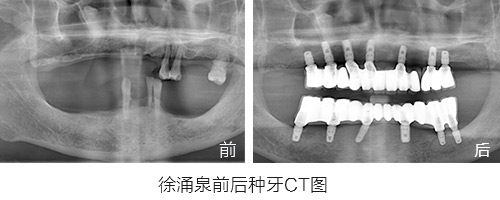

第一期种植市民“明星案例”回顾:徐涌泉

原苏州市第十七中英语老师,因为牙周炎30多岁就开始缺牙,陆陆续续共佩戴更换了5副假牙,期间多次调整,假牙带来的疼痛和牙龈发炎数不胜数。

缺牙带来最惨痛的经历:因为佩戴假牙讲课和发音十分困难,最后无奈放弃了教师职业而转岗。

种植情况:全口种植,即拔即种,植骨

种牙时间:2015年3月(已种牙1年5个月)

徐先生的种牙笔记:记录一年多的种牙经历